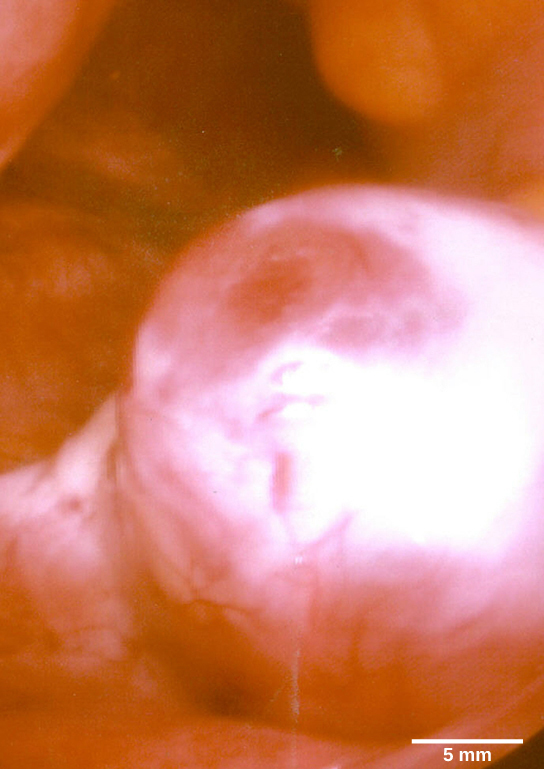

The first half of the ovarian cycle is the follicular phase. Slowly-rising levels of FSH and LH cause the growth of follicles on the surface of the ovary, which prepares the egg for ovulation. As the follicles grow, they begin releasing estrogens and a low level of progesterone. Progesterone maintains the endometrium, the lining of the uterus, to help ensure pregnancy. Just prior to the middle of the cycle (approximately day 14), the high level of estrogen causes FSH and, especially, LH to rise rapidly and then fall. The spike in LH causes ovulation: the most mature follicle ruptures and releases its egg . The follicles that did not rupture degenerate and their eggs are lost. The level of estrogen decreases when the extra follicles degenerate.

Follicle

This mature egg follicle may rupture and release an egg in response to a surge of LH.